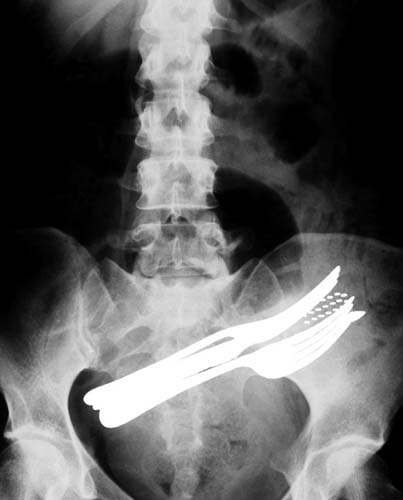

Bu röntgenler gerçek!

İki çatalı, bir tükenmez kalemi ve diş fırçasını yutmuş bir hasta.